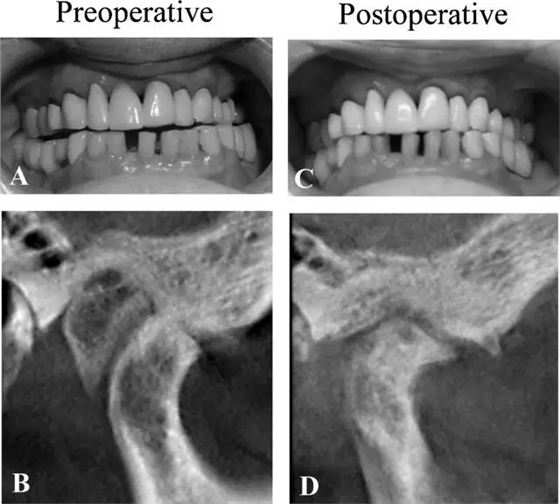

患者,女性,83 歲,晨起自覺右側(cè)顳下頜關(guān)節(jié)疼痛及右側(cè)牙齒無法咬上。檢查發(fā)現(xiàn)下頜左偏 5mm,右側(cè)關(guān)節(jié)區(qū)觸痛,有摩擦音。開口度 26mm。

術(shù)前錐束 CT 見一自顳骨生長的外生骨疣幾乎填滿整個右側(cè)關(guān)節(jié)窩,約有 14 mm × 20 mm × 19 mm,髁突前下方扁平,骨皮質(zhì)不規(guī)則,呈骨關(guān)節(jié)炎影像。髁突后部見有骨沉積,關(guān)節(jié)間隙減小。

圖 2. 病例 2 的口內(nèi)照及 CT 圖像 (A,B) 術(shù)前 (C,D)術(shù)后

術(shù)后愈合良好,無明顯并發(fā)癥,病理檢查證實為骨軟骨瘤。術(shù)后 1 年影像學(xué)檢查發(fā)現(xiàn)髁突位置較術(shù)前更靠近關(guān)節(jié)窩中心,關(guān)節(jié)間隙增大,關(guān)節(jié)窩后部可能殘留有較小的骨軟骨瘤,術(shù)后 1 年及 3 年臨床檢查下頜中線對齊及恢復(fù)咬合,無關(guān)節(jié)區(qū)疼痛,開口度增加到 35mm。